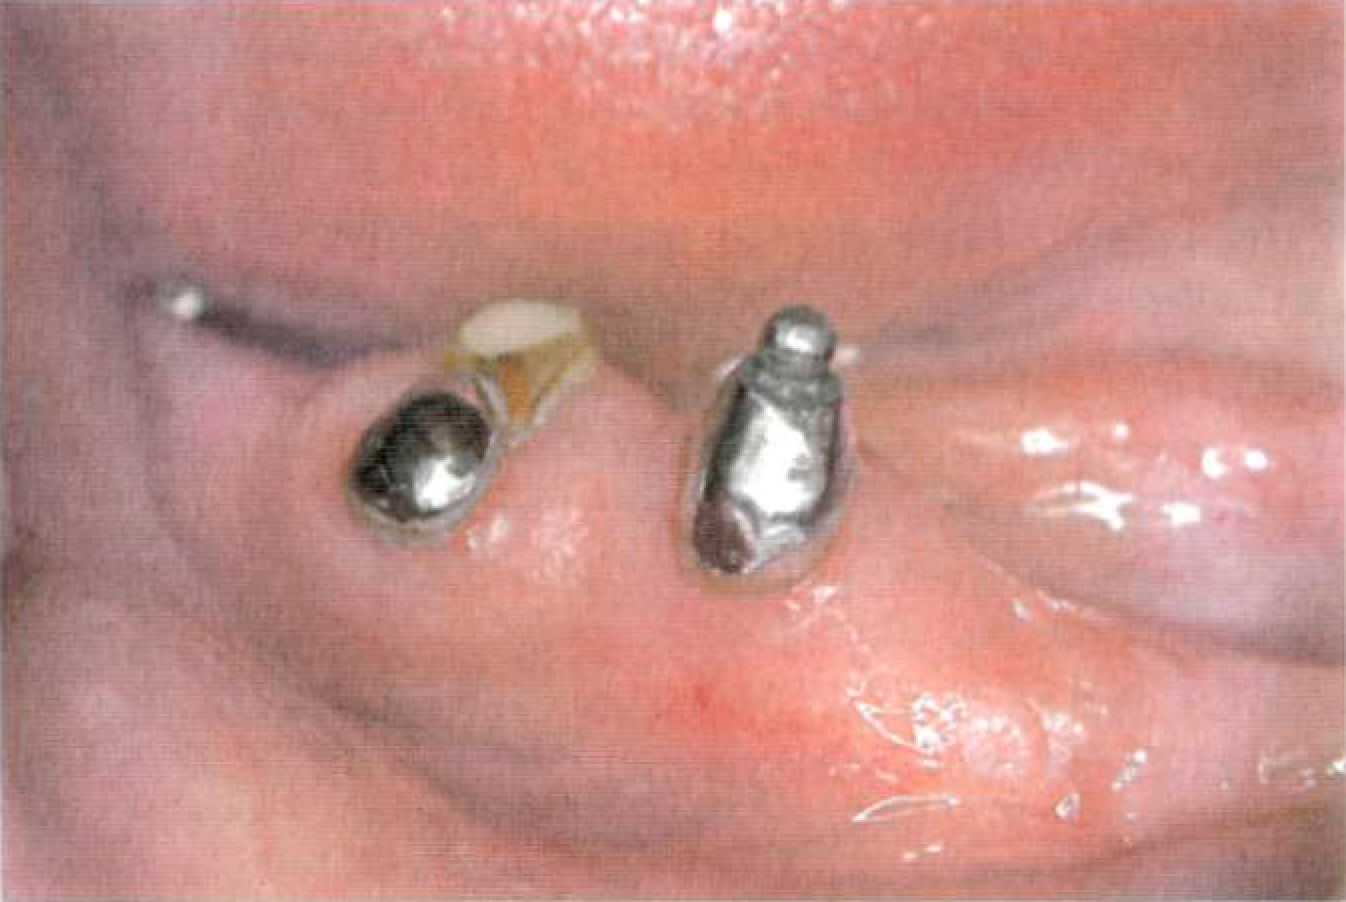

Этап 11. Фиксация культевой вкладки с супрарадикулярным аттачменом на цемент проводится под контролем съемной части (рис. 147). Наложение протеза сопровождается рекомендациями о пользовании протезом, правилах гигиены и сроках контрольных осмотров. Одним из осложнений при применении покрывных протезов с супрарадикулярными аттачменами является развитие кариеса корня (рис. 148). В первую очередь, это происходит из-за неудовлетворительной гигиены полости рта, так как пациенты этой группы — чаще всего достаточно пожилые люди.